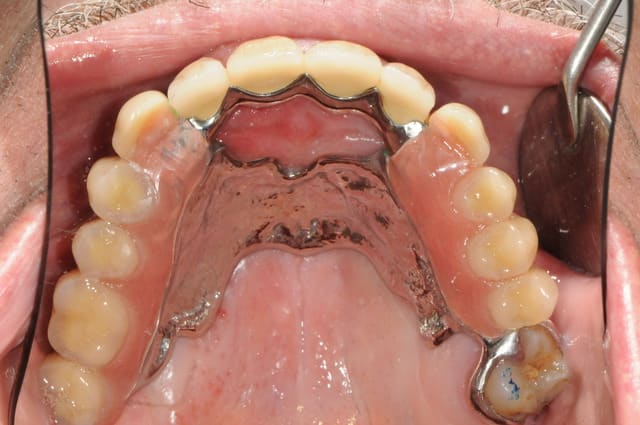

un ptit exemple...

( pardon , je l'avais déjà posté sur nonol mais je ne retrouvais plus le lien...)

pour la petite histoire, le patient voulait seulement une stabilisation de sa prothèse amovible.

les couronnes c'est moi qui lui ai imposé car il fallait rétablir un plan occlusale convenable.

comme les moyens financiers n'étaient pas au rdv une PACSI n'était pas possible.

sa mutuelle lui a très très bien pris en charge ses couronnes et une parti de ses implants. De plus il ne souhaitait vraiment pas extraire les dents antérieurs...

il est tout de même content, mais c'est parfois dure de trouver une solution qui puisse correspondre aux attentes du patient tout en prévoyant l'avenir. quand il le souhaitera, je mettrai deux implants de plus pour passer en prothèse fixe, et dans le pire des cas, pas d'implants supplémentaires, mais un complet stabilisé sur 4 implants.